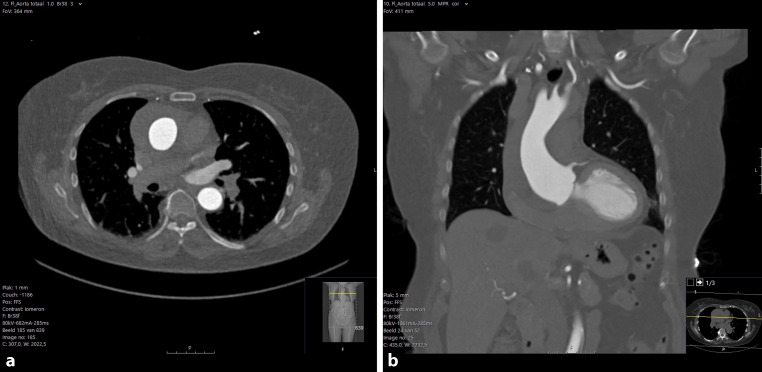

主动脉ct扫描后突然出现胸痛。

Sudden onset chest pain after a CT-scan of the aorta.